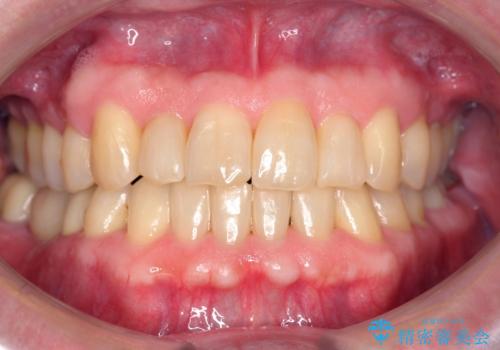

海外留学をしながら歯並びを整えたい インビザラインによる矯正治療

【モニター】 インビザラインによる後戻りの再矯正治療

前歯のデコボコを治したい ワイヤー矯正

前歯のがたつき・すれちがい咬合を非抜歯で。流行の、格安マウスピースでは難しい、ワンランク上の治療